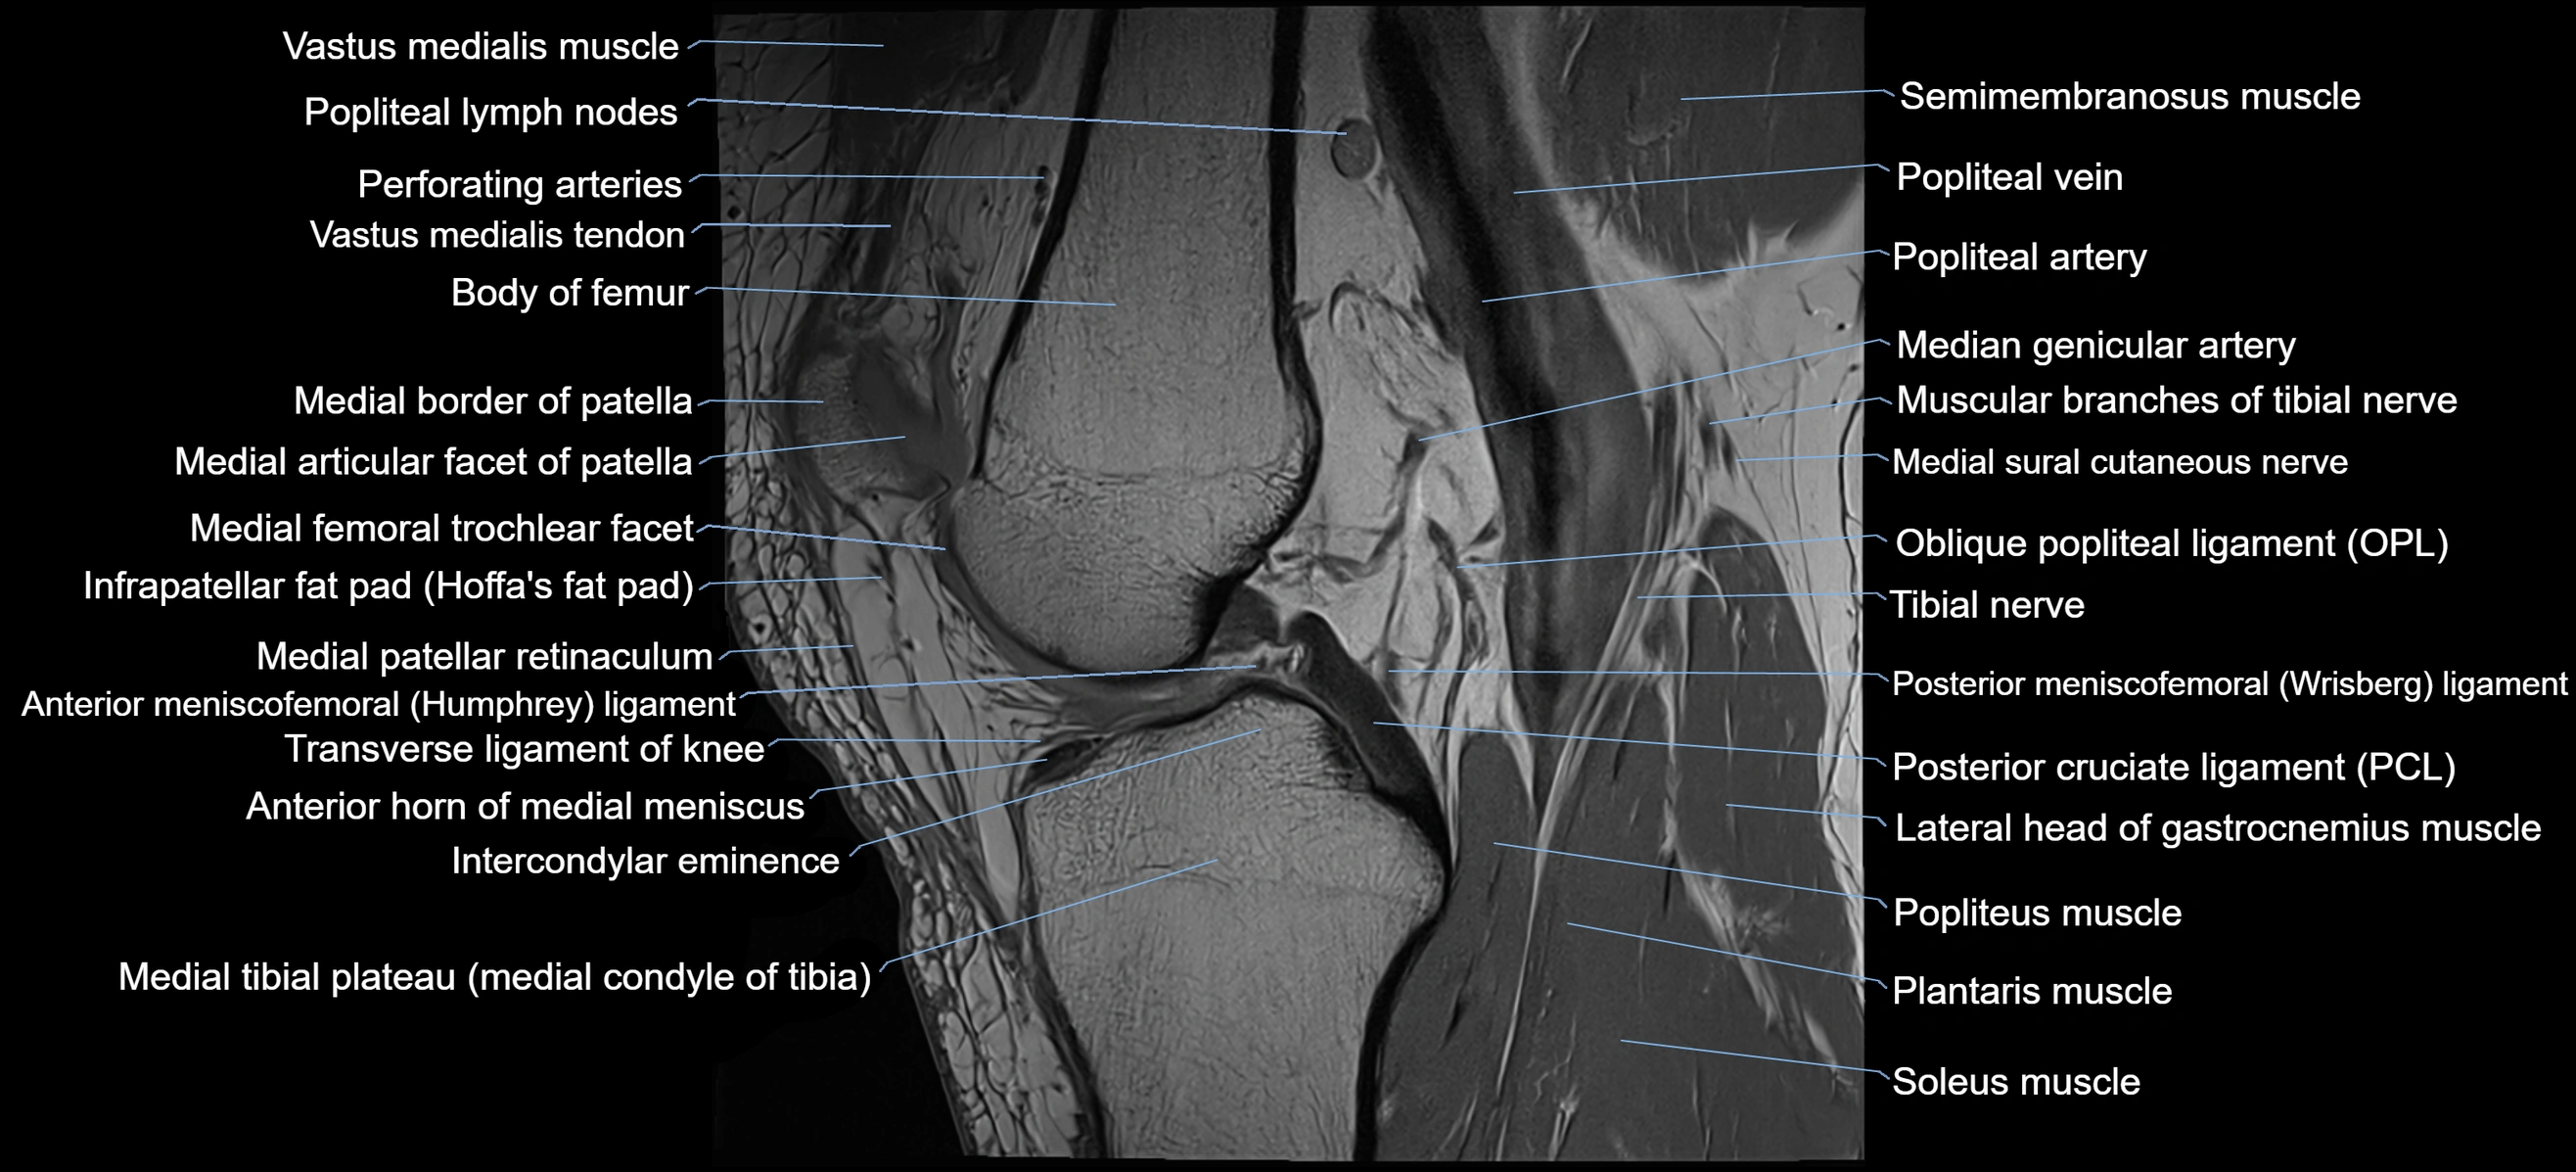

- Anterior horn of medial meniscus

- Anterior meniscofemoral ligament

- Body of medial meniscus

- Infrapatellar fat pad

- Medial articular facet of patella

- Medial border of patella

- Medial head of gastrocnemius muscle

- Medial patellar retinaculum

- Medial sural cutaneous nerve

- Muscular branches of tibial nerve

- Oblique popliteal ligament

- Plantaris muscle

- Popliteal artery

- Popliteal lymph nodes

- Popliteal vein

- Popliteus muscle

- Posterior cruciate ligament

- Posterior meniscofemoral ligament

- Prefemoral fat pad

- Soleus muscle

- Suprapatellar fat pad

- Tibial nerve

- Transverse ligament of knee

- Vastus medialis muscle